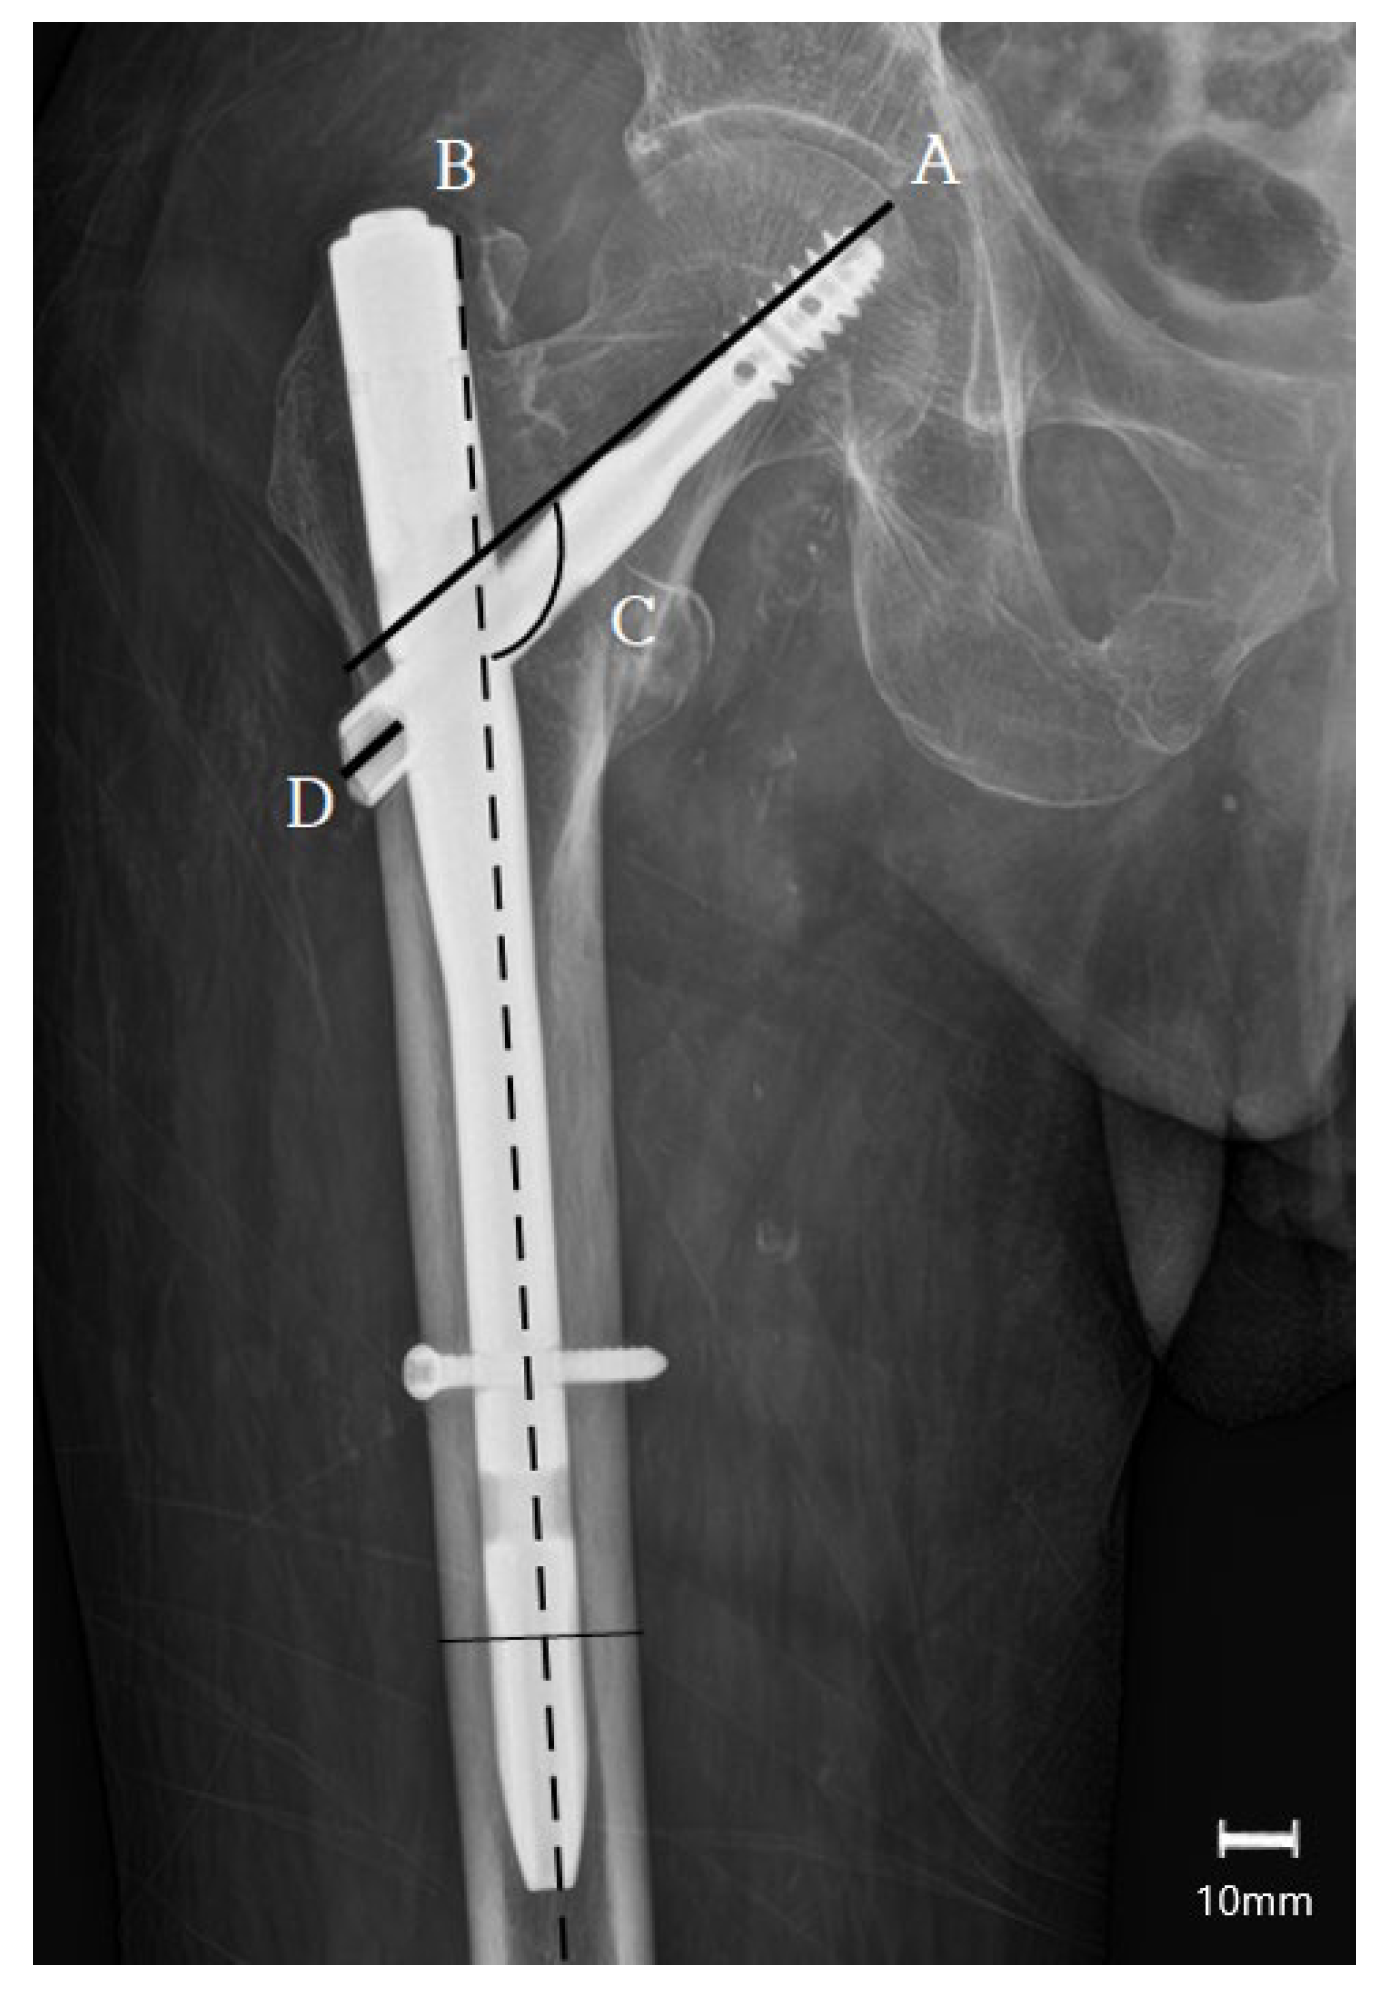

- Chinzei, N.; Hiranaka, T.; Niikura, T.; Fujishiro, T.; Hayashi, S.; Kanzaki, N.; Hashimoto, S.; Sakai, Y.; Kuroda, R.; Kurosaka, M. Accurate and Easy Measurement of Sliding Distance of Intramedullary Nail in Trochanteric Fracture. Clin. Orthop. Surg. 2015, 7, 152–157. [Google Scholar] [CrossRef] [PubMed]

| Lagscrew sliding, mm (mean ± SD) | 2.8 ± 2.1 | 5.4 ± 3.2 | 0.01 * |

| Varus collapse (Δ neck–shaft angle), degrees (mean ± SD) | 3.3 ± 4.6 | 8.2 ± 5.3 | 0.02 * |